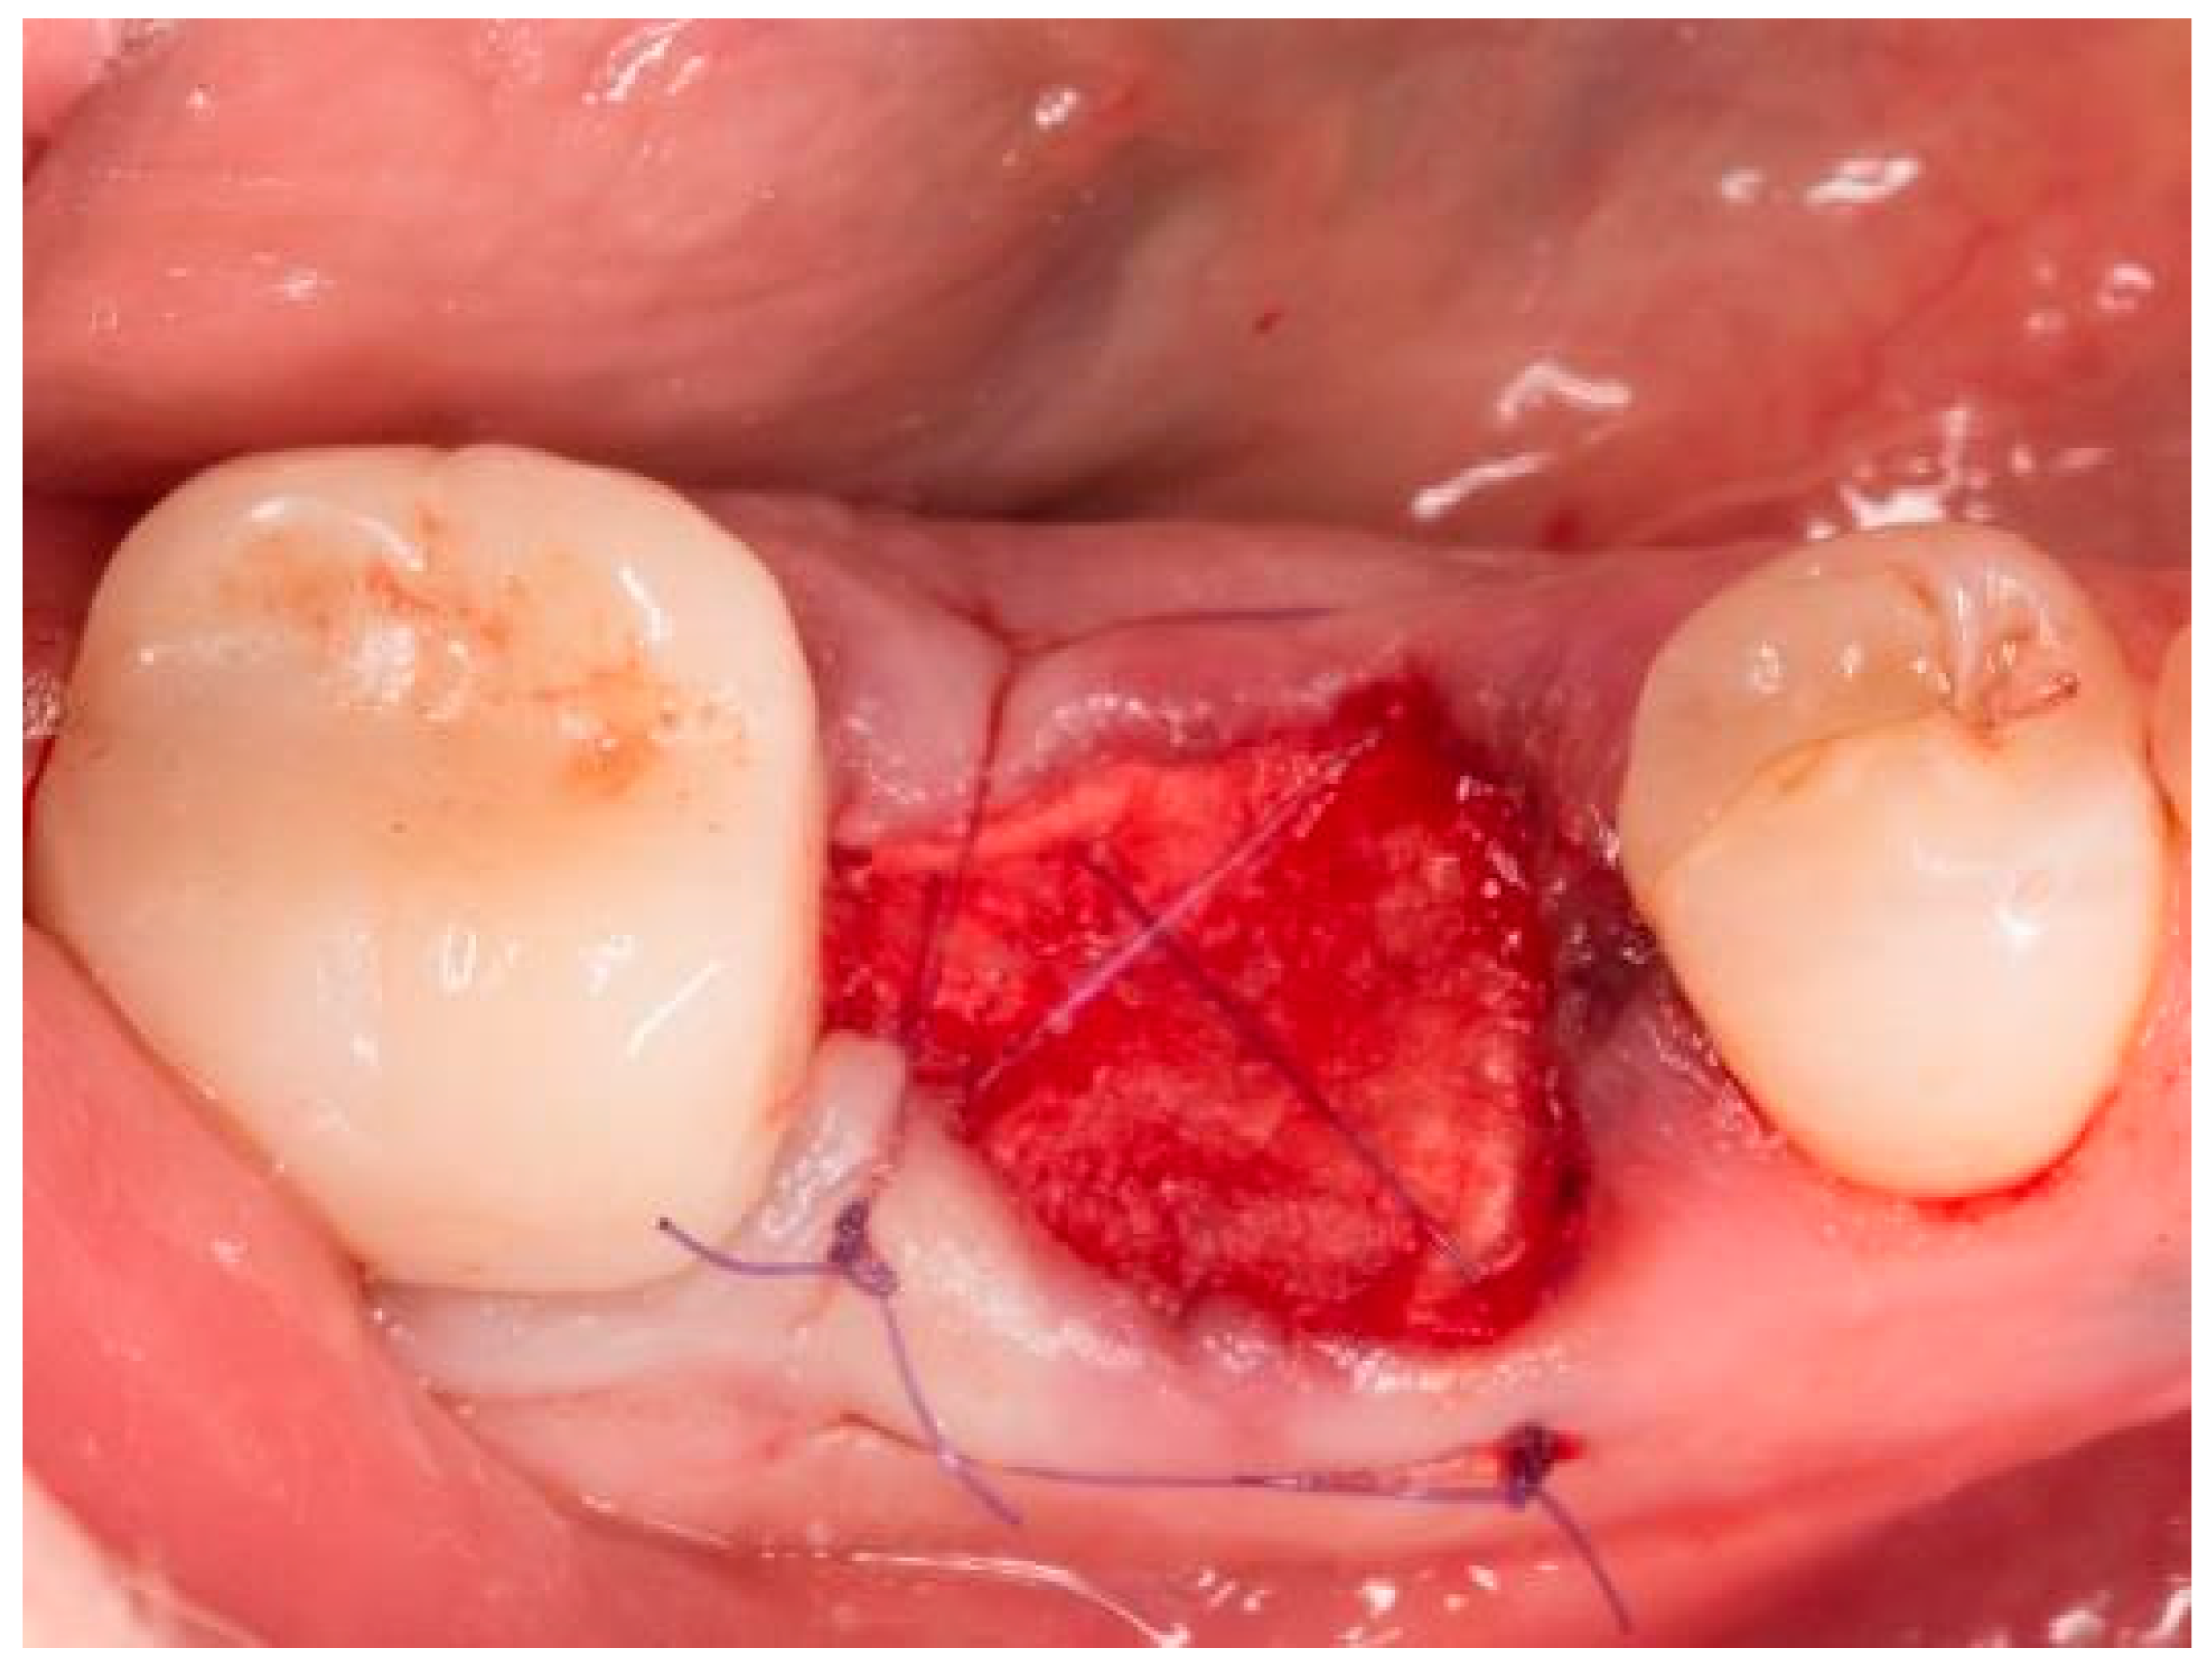

2. Materials and Methods